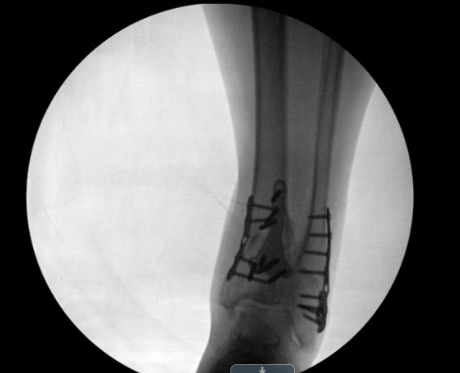

Ankle fracture repair